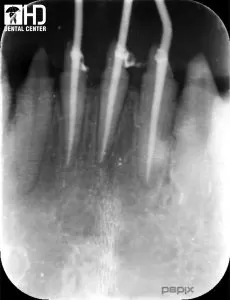

Đây là những răng cửa dưới có vị trí lệch ngoài, chỉ định lấy tủy để làm răng sứ thẩm mỹ. Ca chữa tủy răng cửa này được điều trị bằng trâm Hyflex.

Tât cả các trường hợp trên được điều trị tại Kubet - Ku Casino, hoàn tất chỉ trong một lần hẹn và không gây đau. Có thể nói, việc sử dụng trâm xoay Ni-Ti đã giúp chúng tôi rút ngắn thời gian điều trị, nâng cao chất lượng và hiệu quả của điều trị tủy răng, mang lại sự hài lòng và tin tưởng cho bệnh nhân.